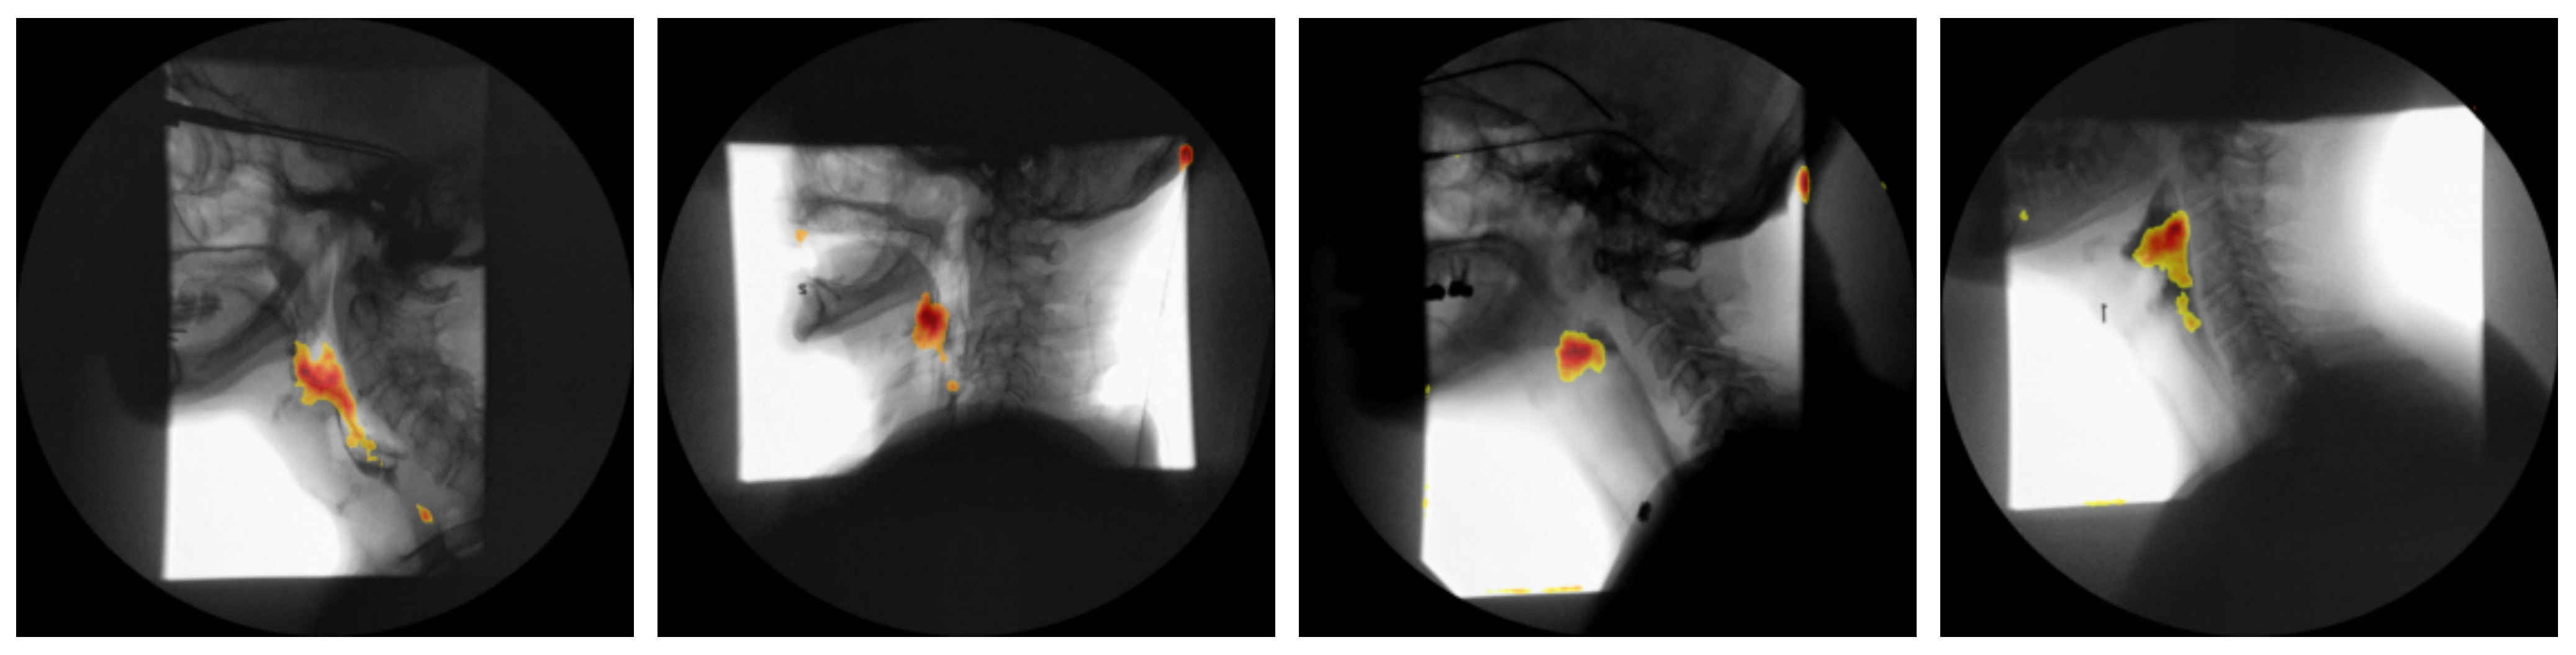

Attention Maps: To elucidate the spatio-temporal evidence leveraged by our vision transformer classifier, we extracted the self attention matrices A l h R N × N from every head h at each layer l. Following the relevance propagation scheme of Chefer et al. [27], the attention matrices were recursively multiplied to obtain a single relevance vector for the class token, which was then reshaped to the original P × P patch grid and bilinearly up sampled to full resolution. For every video frame t, the resulting saliency map m t ( x , y ) was normalized to [ 0 , 1 ] and weighted by the frame wise softmax confidence ω t . The cumulative contribution map M ( x , y ) = t = 1 T w t m t ( x , y ) was thresholded at the 90 th percentile to generate a mask Ω . The mask was finally superimposed on a representative “quiescent” frame (mean optical flow < 0.5 px) to minimize motion artifacts and facilitate anatomical interpretation. Figure 5 presents the attention maps generated for four representative subjects.

As shown in Figure 5, the attention-rollout maps produced by our transformer model consistently demarcate two key anatomical regions: the oropharynx and the hypopharynx. These areas are among the key regions SLPs scrutinize when assessing for penetration, aspiration, or post-swallow residue during VFSS. Notably, earlier study employing Grad-CAM in convolutional neural networks designed for airway-invasion detection has reported analogous localization patterns [28]. However, our findings indicate that transformer-based attention rollout not only recovers this clinically relevant region but does so with markedly higher spatial precision and contrast, yielding sharper, more anatomically accurate saliency maps. This improvement in fidelity aligns with recent advances in transformer explainability, which demonstrate that multi-headed self-attention mechanisms can capture long-range dependencies and fine-grained spatial cues more effectively than convolutional counterparts. Consequently, the present work underscores the potential of transformer architectures to enhance interpretability in medical imaging applications, providing saliency visualizations that are both biologically meaningful and diagnostically actionable.

Figure 5. Attention-rollout saliency maps from the proposed ViT on four representative VFSS subjects overlaid on a “quiescent” frame (low optical flow). Warm colors consistently localize the oropharynx and hypopharynx, demonstrating precise, anatomically faithful localization.